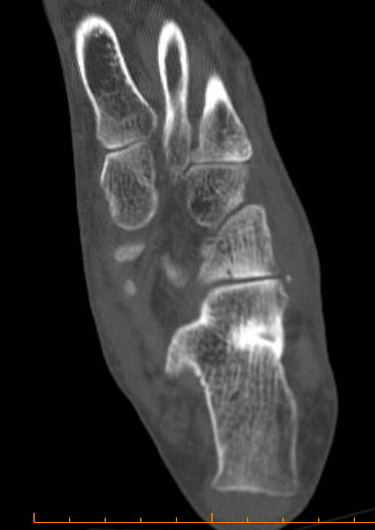

¹ßµî Lisfrang °üÀý Ⱦ´Ü¸é °Ë»ç¿¡¼­ Á¦2 ÁßÁ·°ñ ±âÀúºÎ °ß¿­°ñÀýÀÌ °üÂûµÈ´Ù(»çÁø 7).